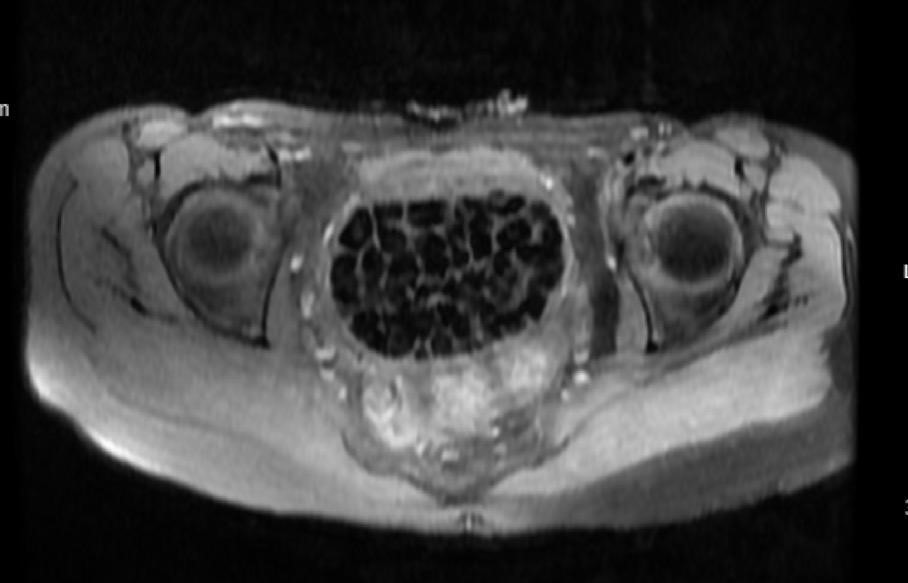

Hastasının durumunu değerlendiren Üroloji Uzmanı Doç. Dr. Erkan Erkan, "Hastamızın 2004 yılında doğduğunu ardından doğar doğmaz ekstrofi vezika dediğimiz 50 binde bir görülen bir anomaliden dolayı art arda ameliyatlar geçirdiğini öğrendik. 10 yaşında yine bir ameliyat geçirmişti, gerekli görüntüleme ve tetkiklerimizi yaptırdık. Normalde mesanesinin olması gereken yerin hemen arka kısmında taşlarla dolu bir kese olduğunu gördük, bunun üzerine ek görüntülemeler; MR çektirdik. Hastamız çelişkili açıklamalar almıştı, kendi radyolojik kliniğimiz ve edindiğimiz konsültasyonlarda taşların mesanede değil vajinal boşlukta oluştuğunu düşündük, bir planlama yaptık.

Genç kızın uzun süredir karın ağrısı çektiğini belirten Jinekolojik Onkoloji Uzmanı Op. Dr. Emin Erhan Dönmez, "Mesane taşları olduğu düşünülerek daha büyük bir hastaneye refere edilmiş. Aramızda mini bir konsey yaparak muayene ettik. Vajen bir hazne görevi görerek orada durağan bir idrar, uzun süre beklediği için idrar içindeki minerallerde çökerek taşlar oluşmuş. Mesanedeki idrarın vajene akmış olabileceği ve vajende göllenen idrar nedeniyle taşların burada oluşacağını düşündük, ameliyatımızı planladık. Ameliyata tanı amaçlı girmiştik, sistoskopi (Mesane gibi idrar yollarını kapsayan kısımlardaki rahatsızlıkların teşhis ve tedavisinde kullanılan endoskopik bir yöntem) dediğimiz ameliyatı Erkan Hocam ile birlikte gerçekleştirdik.

Önce mesaneyi bir görüntüledik, mesane tabanına yaklaşık 2-3 cm’lik bir alandan vajene fistülize olduğunu gördük. Mesaneden vajene geçtiğimiz esnada tüm vajenin taşlarla dolu olduğunu gördük. Tanı amacıyla girdiğimiz ameliyatta her şey de olağan gittiği için tedaviye geçtik. Taşların çıkabileceği kadar bir genişlik sağladık. Daha sonra yaklaşık en büyüğü 2,5 cm boyutlarında olan, irili ufaklı 287 tane taşı ameliyat esnasında çıkarmış olduk. Taşların tekrarlamaması için idrarın göllenmemesi, en azından dışarıya rahatça boşalabilmesi için vajinal rekonstrüksiyonu sağladık. Ameliyatta da herhangi bir problem yaşamadık. Literatürü Erkan Hocam ile birlikte değerlendirmiştik. Primer olarak vajende birikmiş olan bu kadar çok sayıda taşla ilgili bir makale görmedik, rastlamadık" dedi.